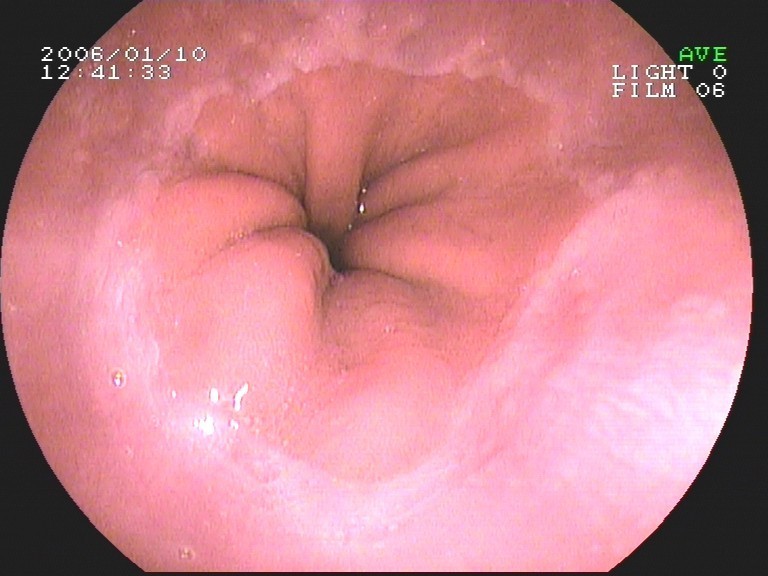

Coloskopie - Valvula Bauhini (Dünndarmklappe)